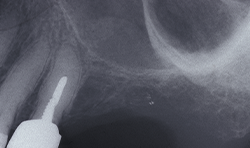

The Magnetic Max (Figs. 1-2) is useful for conservative root extraction.

Fig. 1

Fig. 2